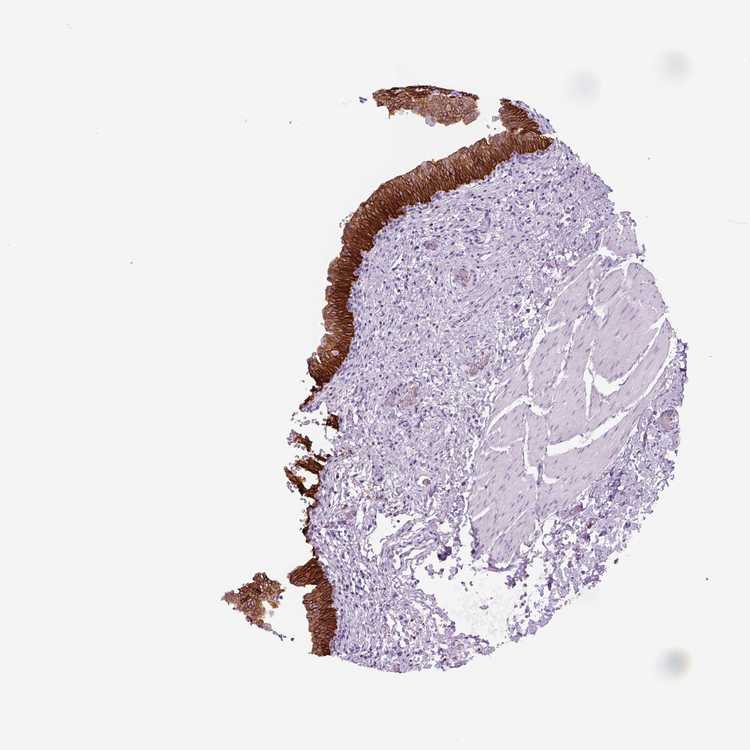

URINARY BLADDER - Antibody stainingi

Antibody staining in the annotated cell types in the current human tissue is reported as not detected, low, medium, or high, based on conventional immunohistochemistry profiling in selected tissues. This score is based on the combination of the staining intensity and fraction of stained cells.

Each image is clickable and will lead to virtual microscopy that enables deeper exploration of all samples and also displays staining intensity scores, fraction scores and subcellular localization as well as patient and tissue information for each sample.

Antibody HPA014924

Urothelial cells High